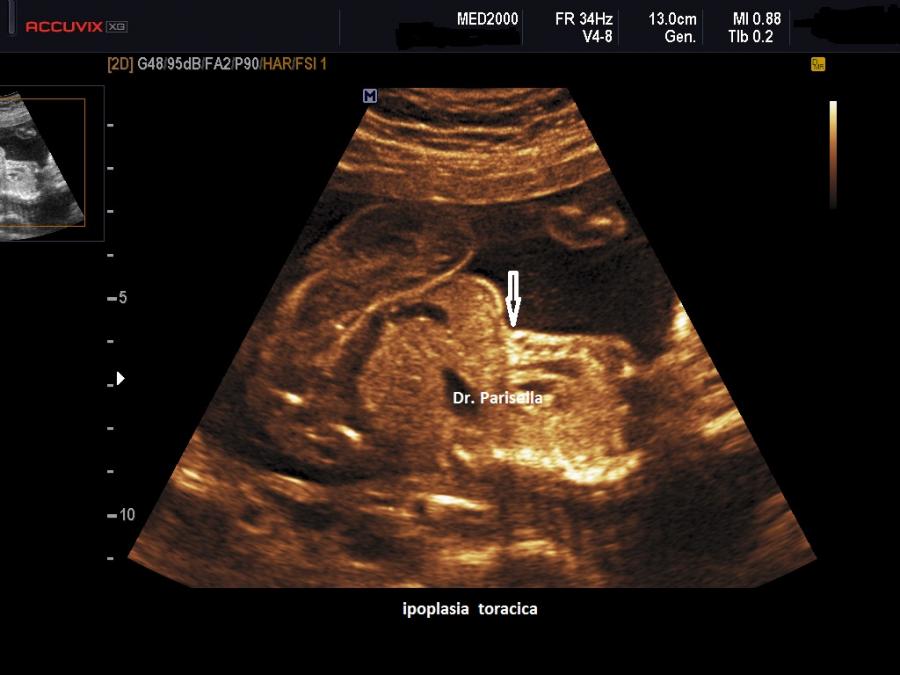

Il quadro malformativo conseguente alla sequenza ipo-acinesia-deformazione-fetale è legato ad una sequela di eventi caratteristici: a livello degli arti inferiori i gruppi muscolari più potenti sono gli estensori per cui gli arti inferiori saranno estesi e i piedi torti avranno un atteggiamento equino-varo; agli arti superiori prevalgono i muscoli flessori per cui le braccia saranno flesse davanti al torace, mani chiuse a pugno e in deviazione ulnare con clinodattilia; la paralisi del diaframma e dei muscoli respiratori sarà responsabile dell'ipoplasia toracica e polmonare; il blocco dell'articolazione temporo-mandibolare determina micrognazia; il blocco dei muscoli orbicolari determina microstomia. Ovviamente l'evento funzionale più evidente all'esame ecografico sarà rappresentato dall'assenza di movimenti attivi fetali.

5) ipoplasia toracica;